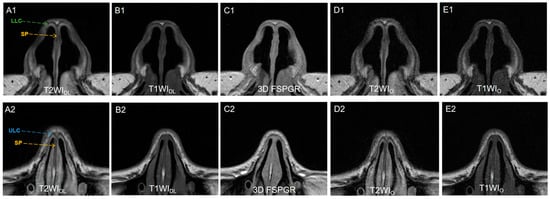

The results showed a significant difference of qualitative characteristics (noise, contrast, and artifacts) between FSEDL (including T1WIDL and T2WIDL) and FSEO (including T1WIO and T2WIO), as well as between FSEDL and 3D FSPGR (Both p < 0.001). Figure 3 illustrates different slices of image sets for one pre-rhinoplasty 25-year-old female patient. FSEDL images showed less noise and artifacts, as well as better contrast (p < 0.001), compared to FSEo and 3D FSPGR. The overall image quality between T1WIDL and T2WIDL showed no significant difference (p = 0.655). Identification of anatomical structures on FSEDL was significantly better than on FSEO and 3D FSPGR (all p < 0.001). Anatomy display of LLC and SP was optimal on T2WIDL followed by T1WIDL and 3D FSPGR, while no significantly different display of ULC were observed for T1WIDL and 3D FSPGR (p > 0.05). Inter-rater agreement of qualitative assessment was fair to excellent (all κ > 0.61, Table 3). The mean scores of image quality for all series of two raters are presented in Figure 4.

Figure 3.

(A1,A2) T2WIDL (DLR T2-weighted FSE images), (B1,B2) T1WIDL (DLR T1-weighted FSE images), (C1,C2) 3D FSPGR (three-dimensional fast spoiled gradient-recalled images), (D1,D2) T2WIO (original T2-weighted FSE images), and (E1,E2) T1WIO (original T1-weighted FSE images) in axial view of a 25-year-old female nasal cartilage. The overall image quality and contrast of FSEDL images showed better than any other image sets because of less noise. T2WIDL showed the best anatomical structure of nasal cartilage for higher contrast. No significantly different display of ULC between T1WIDL and 3D FSPGR was observed (p > 0.05) while 3D FSPGR showed relatively poor image quality of SP. DLR = deep-learning-based reconstruction, SP = septal cartilage (yellow dashed arrow), LLC = lower lateral cartilage (green dashed arrow) and ULC = upper lateral cartilage (blue dashed arrow).